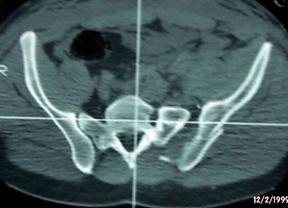

Fractura Malgaigne Fractura Malgaigne. Imagine CT

Fractura de

aripa iliaca stanga Fractura de aripa iliaca

stanga